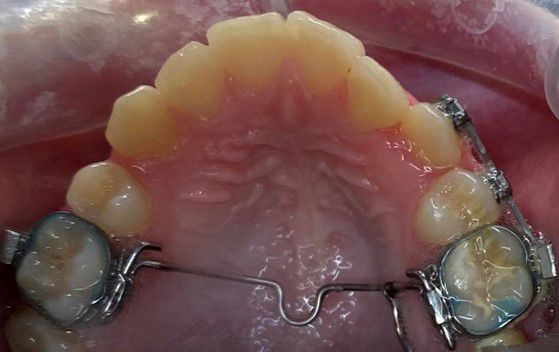

Sidder på tandbånd og ligger langs ganen, for at holde eller ændre på 6-års tænderne i overkæben. Desuden kan den holde eller øge tandbuens bredde.

Bruges til at udvide tandbuen i overkæben, f.eks. ved krydsbid.

Den er fastgjort til 6-års tænderne med 2 bånd.

Bruges til at udvide ganen.

Den limes fast på tænderne. Der skal skrues i midten af bøjlen, I får en grundig instruktion på tandreguleringsklinikken.